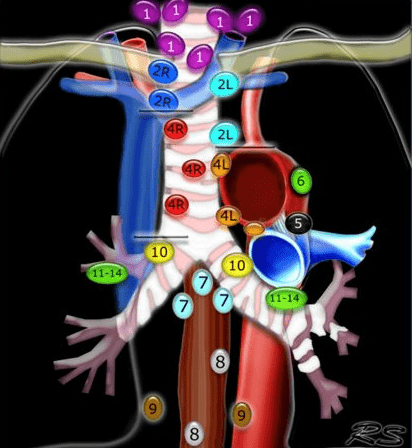

2R on the IASLC Lymph Node Map is considered which lymph node location.

Upper paratracheal (will also accept superior mediastinal).